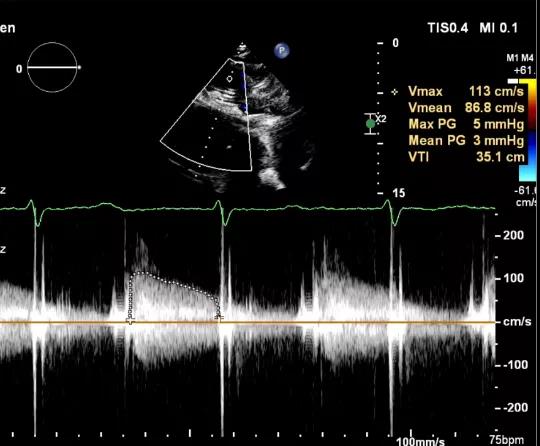

食道超声评估

三尖瓣术前平均压差9mmHg

三尖瓣瓣中瓣术后平均压差3mmHg